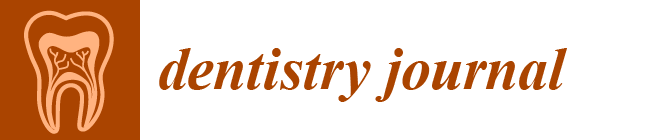

2.1. Case 1

2.2. Case 2